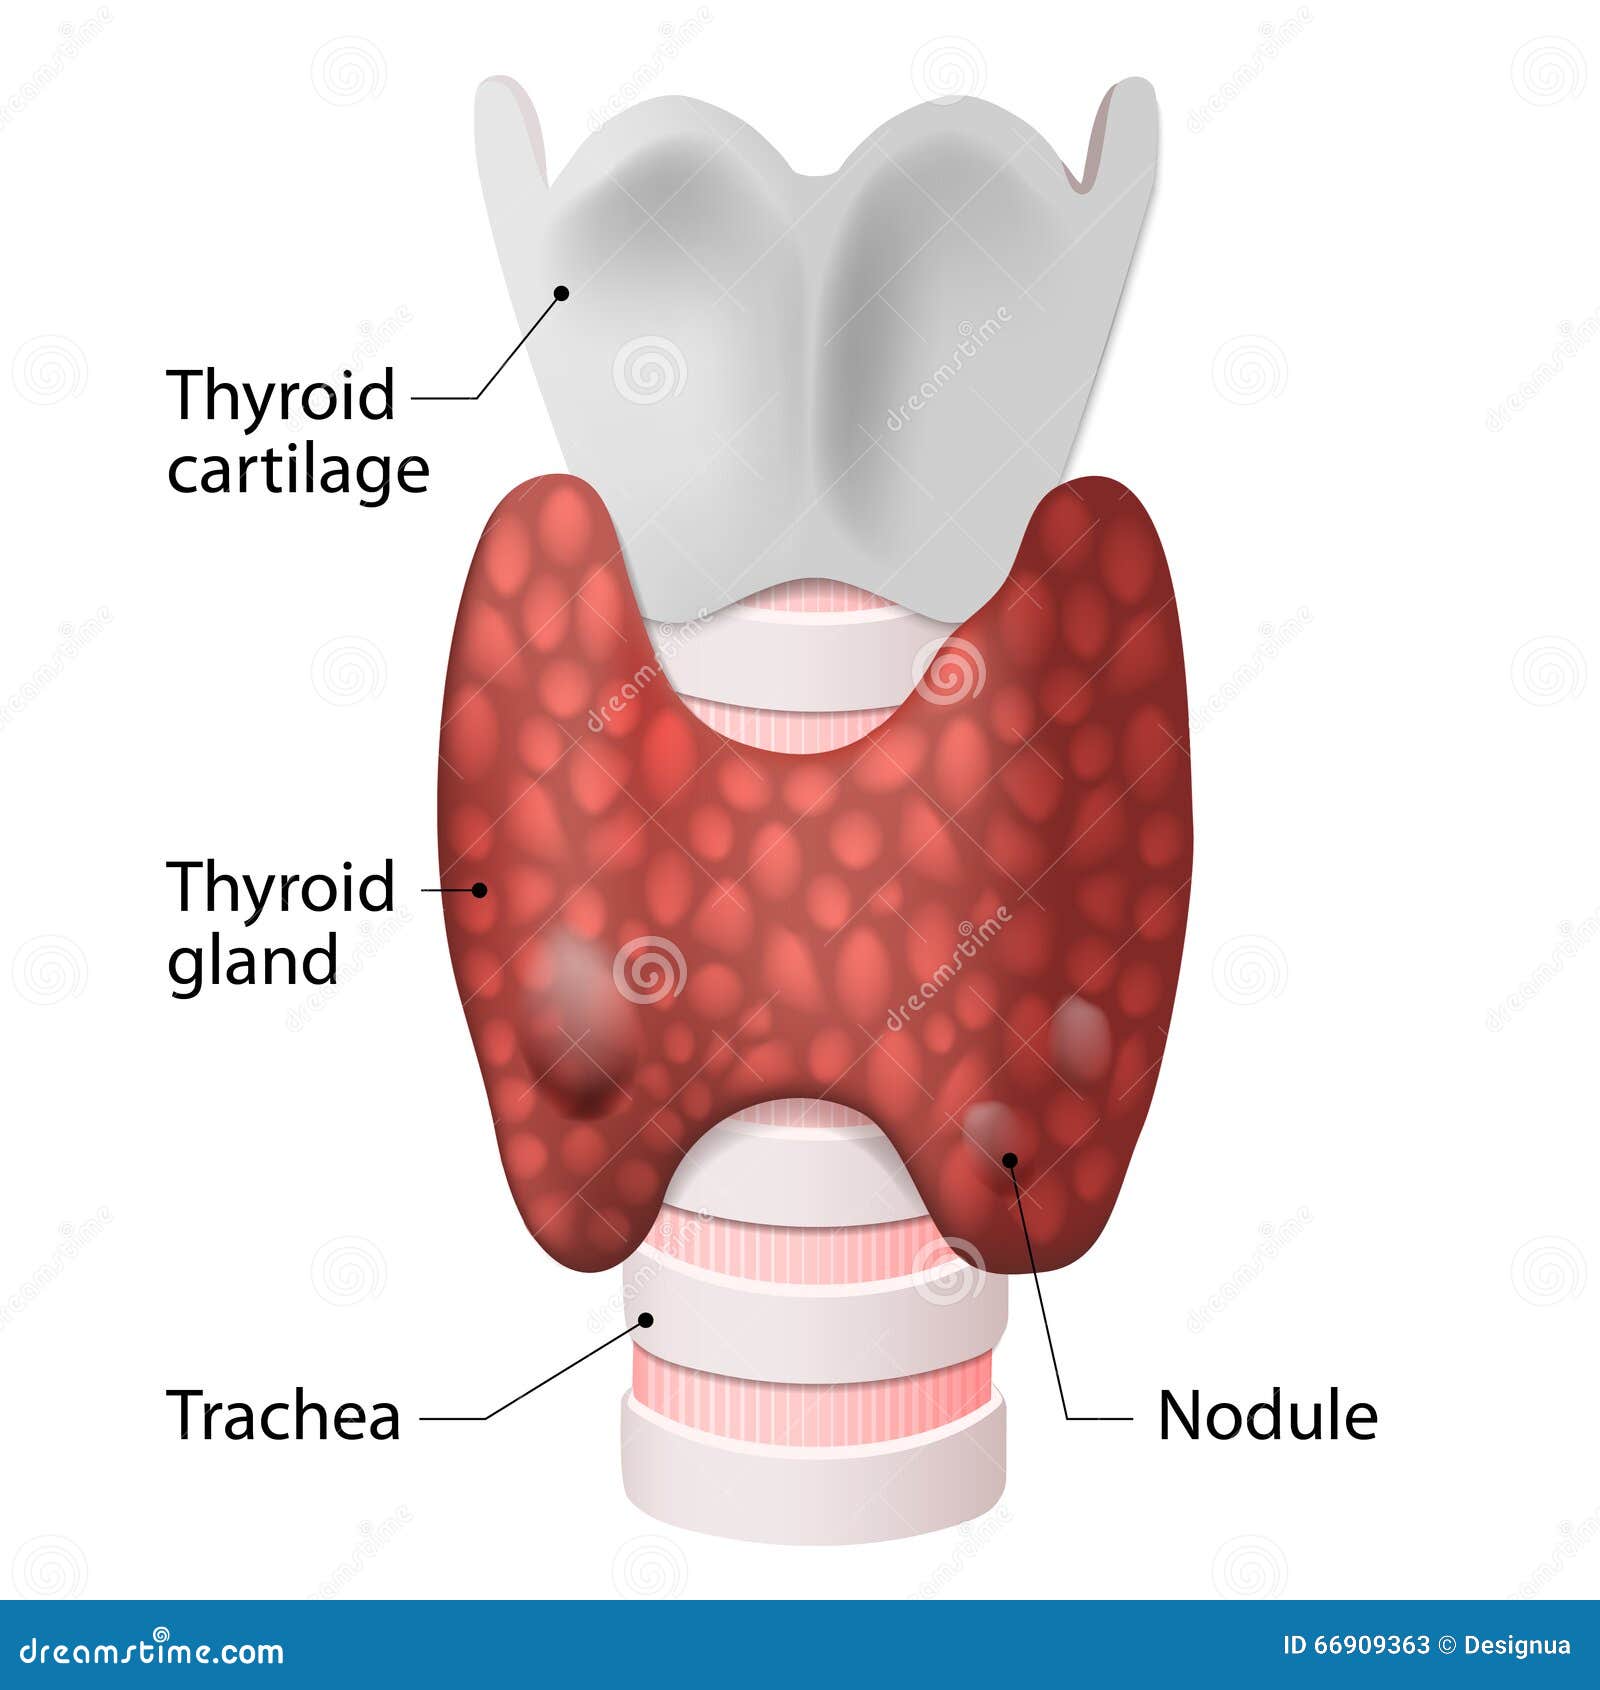

THYROID Stock Photo CartoonDealer 76650228

https://thumbs.dreamstime.com/z/thyroid-nodules-goiters-anatomy-gland-included-throat-gland-trachea-66909363.jpg

Thyroid Nodules

Thyroid Nodules